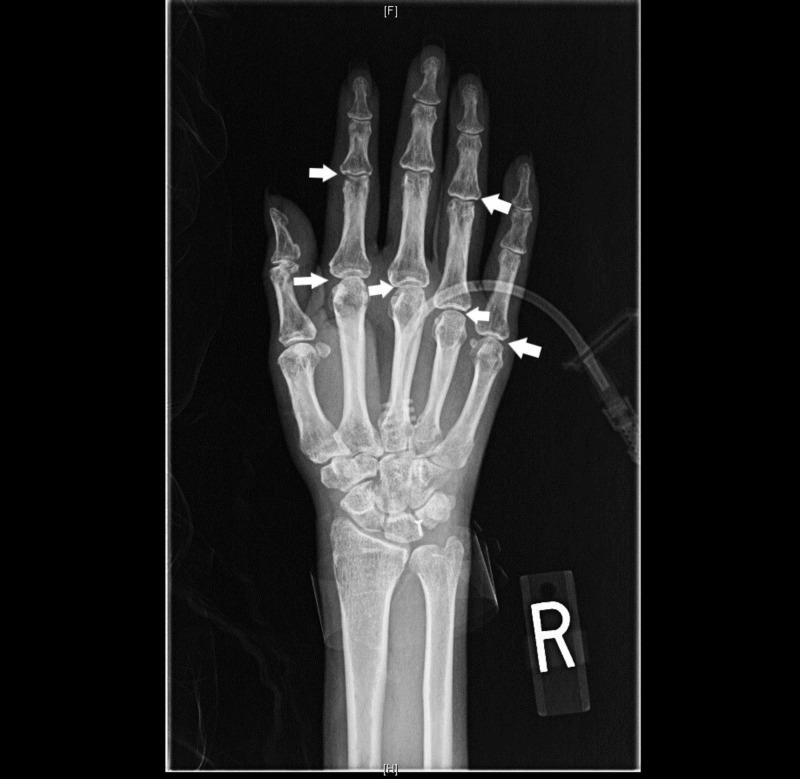

A 49-year-old lady with no past medical history presented with dysphagia and 40-pound weight loss, which occurred over eight months. On physical examination, she had proximal muscle weakness and crackles in basilar regions of the lungs. Labs were significant for low albumin, elevated transaminases, and high aldolase. Imaging suggested aspiration pneumonitis in both lungs and hepatic steatosis. A swallow evaluation revealed oropharyngeal dysphagia and muscle biopsy confirmed a rare form of myositis. A liver biopsy showed steatohepatitis and a diagnosis of starvation-induced steatohepatitis was made. The patient succumbed to hypoxic respiratory failure from aspiration pneumonitis before the treatment for myositis could be initiated. We report the first case of starvation-induced steatohepatitis in a patient with dysphagia from myositis affecting the oropharyngeal musculature.